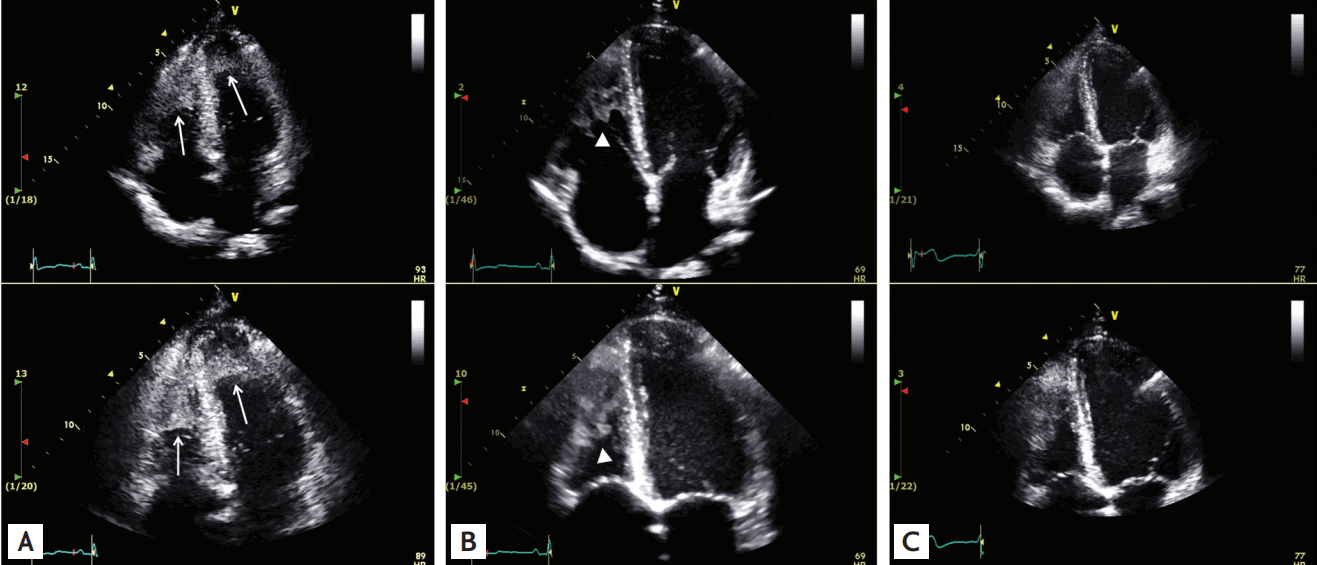

Figure 1.

Serial transthoracic echocardiogram (TTE) in apical 4-chamber view. (A) Initial TTE images demonstrate large echodense masses attached to significantly thickened biventricular endocardial walls (white arrows). (B) After 15 days of treatment (warfarin and imatinib), TTE demonstrated complete regression of echogenic wall thickening in the left ventricular apex, but was still noted in the right ventricular apex (arrowheads). (C) Follow-up TTE was performed after 3 months of treatment, with no further evidence of wall thickening or thrombi in both ventricular apices.

A 28-year-old man presented to the emergency department with a headache, dyspnea, and aphasia. Acute infarction in the left posterior middle cerebral artery territory was found on brain magnetic resonance imaging. A transthoracic echocardiogram revealed endocardial thickening and thrombus in both ventricular apices, typical finding of Loeffler endocarditis (Fig. 1A). Initial laboratory findings were as follows: hemoglobin 12.5 g/dL, white blood cell (WBC) count 26,400/µL (eosinophils 12,302/µL), and platelet count 44,000/µL. All antibody tests for parasites were negative and no other allergic symptoms were present. In the bone marrow (BM) aspirate, marked eosinophilia, often with bizarre nuclear lobulation, and dysgranulation were found (Fig. 2A). The biopsy specimen showed hypercellular (90%) marrow for age (Fig. 2B). Fluorescence in situ hybridization (FISH) analysis was positive (92%) for FIP1L1/PDGFRA fusion (Fig. 3A). According to the 2008 World Health Organization classification, he was diagnosed with myeloid and lymphoid neoplasm (CEL) associated with FIP1L1/PDGFRA. Low-dose imatinib (100 mg) and anticoagulation with enoxaparin were started. The WBC, eosinophil and platelet count normalized within 10 days of imatinib treatment. After 2 months of treatment, FISH for FIP1L1/PDGFRA fusion became negative (Fig. 3B). Endocardial thickening and thrombus in both ventricles resolved on serial echocardiography during 3 months of treatment with imatinib (Fig. 1B and 1C). Follow-up BM aspiration and biopsy slides after 3 months of treatment showed normocellular marrow with 1.3% of eosinophil count (Fig. 2C and 2D). The patient remains in complete cytogenetic remission and had no signs or symptoms for over a year.